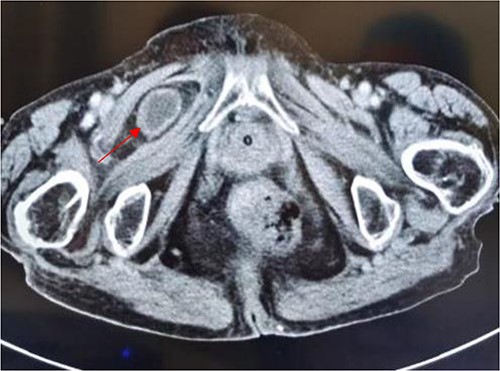

Coronal view shows right obturator hernia entering the intestinal canal (indicated by red arrow).